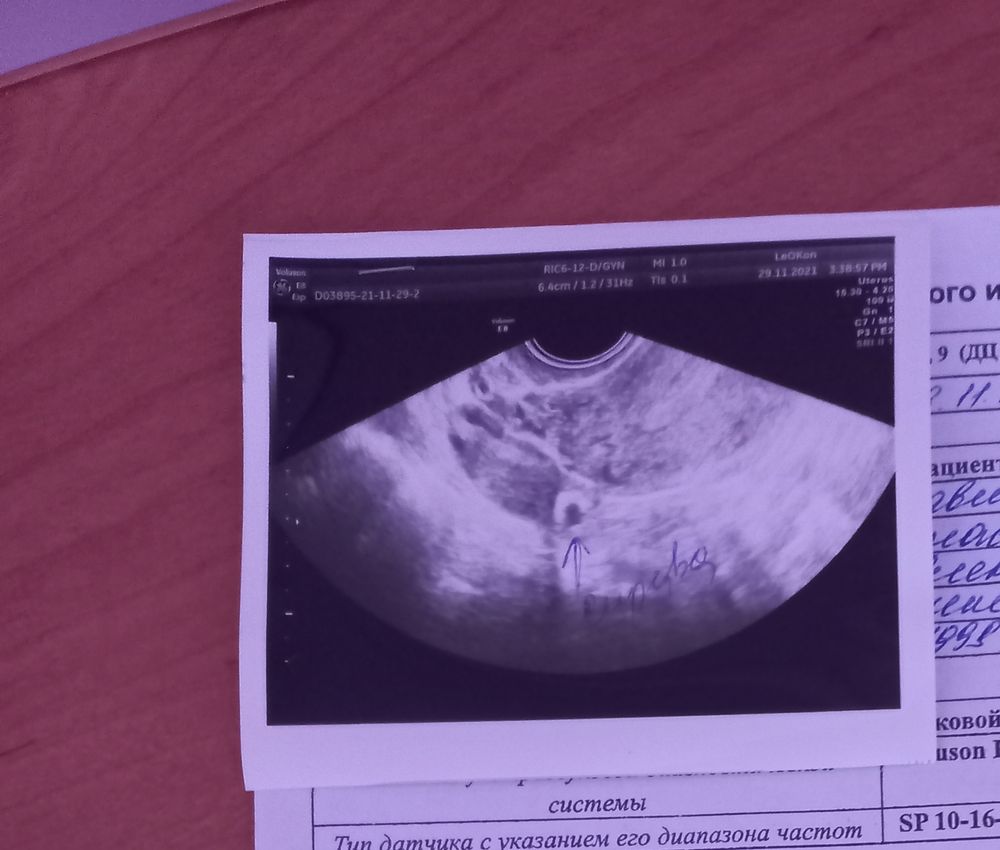

Снимок узи прикрепила. Может быть я чего то не понимаю уже от постоянного чувства тревоги и переживания ВБ или нет. Как то не особо на операционный стол ложиться.